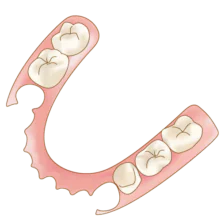

入れ歯・義歯

入れ歯治療は、あらゆる症例に対応できる柔軟性があります。歯型を採取し、取り外し可能な入れ歯を作製します。治療法の歴史も古く、患者にとって身体的な負担が軽いのが特徴です。入れ歯は健康保険適用のものであれば、費用や治療期間も抑えることができます。

入れ歯治療は、あらゆる症例に対応できる柔軟性があります。歯型を採取し、取り外し可能な入れ歯を作製します。治療法の歴史も古く、患者にとって身体的な負担が軽いのが特徴です。入れ歯は健康保険適用のものであれば、費用や治療期間も抑えることができます。